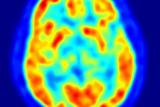

PET/CT扫描可以替代淋巴瘤患者的骨活检吗?

根据2月12日发表在《Cureus》杂志上的研究,在淋巴瘤患者的骨髓癌检测中,FDG-PET/CT扫描可能比侵入性活检更受青睐。 2023-02-17 PET/CT